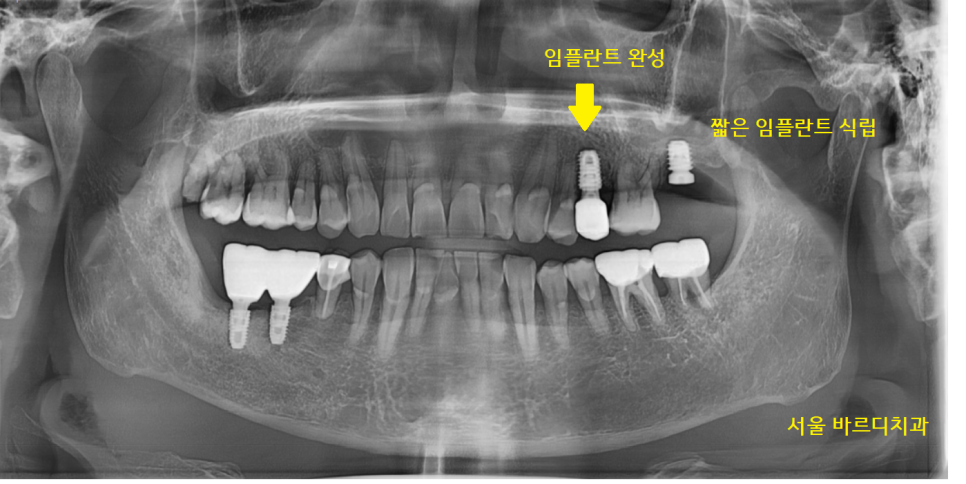

파노라마 상에서 상악동 부위와

치아 뿌리 끝이 엄청 가깝네요~

22.12.28

덕풍동 치과에서

이미 발치가 된 치아는 임플란트 수술을 진행하고

타 병원에서 임플란트 불가 판정을 받은

맨 끝 치아

잇몸 뼈가 부족한 상황이라

발치 후 뼈이식을 먼저 진행했습니다.

23.12.29

사진을 보시더라도

옆에 치아보다

임플란트 길이가 짧은 게 보이시죠?